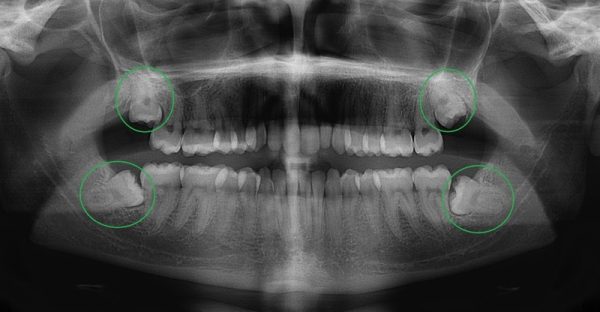

Bước 1: Thăm khám và chụp phim X-quang

Bác sĩ sẽ tiến hành thăm khám và chụp phim X-quang nhằm xác định vị trí và hướng mọc của răng khôn. Nhìn vào kết quả phim chụp, bác sĩ có thể đánh giá tổng quan và lên kế hoạch nhổ phù hợp.

Nha Khoa Jiang trang bị nhiều máy móc hiện đại, ứng dụng vào thăm khám và nhổ răng khôn. Khách hàng sẽ được chụp X-quang để xác định chính xác vị trí răng khôn, hình dáng, phương thế của răng và các dây thần kinh, mạch máu quanh răng.